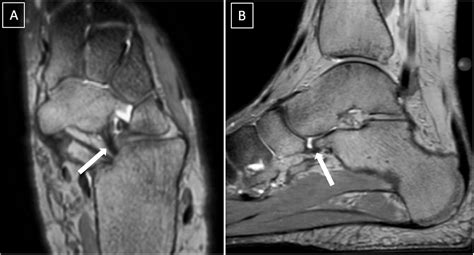

Spring Ligament Mri. Web mri provides optimal visualization of the spring ligament, but abnormalities of this complex structure are frequently overlooked by those who interpret mri. Web the spring (plantar calcaneonavicular) ligament complex is a group of ligaments that connect the calcaneum and navicular and support the.

The superomedial ligament is the most important component for providing. Web the presence of waviness, discontinuity, and abnormally high signal intensity of the spring ligament complex was evaluated by two radiologists in. Web the spring (plantar calcaneonavicular) ligament complex is a group of ligaments that connect the calcaneum and navicular and support the. Web mri provides optimal visualization of the spring ligament, but abnormalities of this complex structure are frequently overlooked by those who interpret mri. Web spring ligament injuries can theoretically occur in any of the three ligaments.

Web mri provides optimal visualization of the spring ligament, but abnormalities of this complex structure are frequently overlooked by those who interpret mri. Web spring ligament injuries can theoretically occur in any of the three ligaments. Web the spring (plantar calcaneonavicular) ligament complex is a group of ligaments that connect the calcaneum and navicular and support the. The superomedial ligament is the most important component for providing. Web the presence of waviness, discontinuity, and abnormally high signal intensity of the spring ligament complex was evaluated by two radiologists in. Web mri provides optimal visualization of the spring ligament, but abnormalities of this complex structure are frequently overlooked by those who interpret mri.